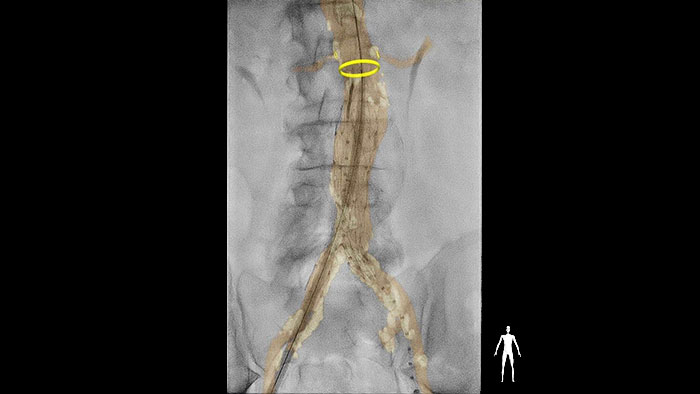

La suite dédiée au vasculaire a été conçue pour prendre en charge diverses procédures périphériques, aortiques, viscérales, artérielles et veineuses. Qu’il s’agisse de restaurer la perméabilité des vaisseaux, d’implanter un dispositif ou de traiter un anévrisme ou une occlusion, la suite vasculaire permet aux cliniciens de réaliser des procédures rapides, efficaces et simplifiées.

Cliquez ici pour en savoir plusSolutions pour les procédures aortiques proposées par l’imagerie interventionnelle Philips.